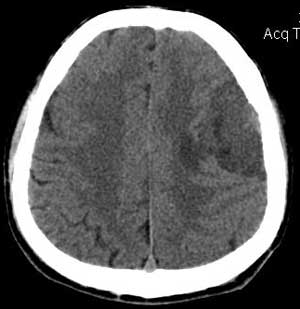

左颞部稍低密度d形肿块影阴,密度不均,内有不规则囊变区,局部脑白质受压塌陷,肿块周围少许水肿带,中线轻度右移位,增强扫描明显强化,局部颅板有轻微侵蚀,如此大的肿块中线结构移位不明显说明肿块位于脑外,如此强化的脑外肿瘤只有一个------脑膜瘤

与颅骨广基相连,不均匀强化,脑白质受压,考虑脑外肿瘤,脑膜瘤。

定位:脑灰白质界面内移,肿瘤位于脑外,应该明确。

定性:支持脑膜瘤。

左侧颞顶叶见d形肿块灶,密度不均,其内可见低密度影,局部脑白质所压移位,病灶明显强化。支持脑膜瘤